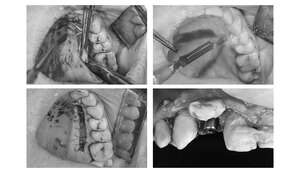

インプラント2本の予定ですので、インプラント同士をほぼ並行に埋入する計画を立てます。神経にインプラントが当たりますと、麻痺が起きたり出血の原因になりますので、

シュミレーション上でもしっかり神経とは距離をおきます。

【担当医師所見】

歯ぐきを切ってインプラントを埋入しました。埋入後は歯ぐきを縫って終わります。

この状態で4ヶ月待ちインプラントと骨の生着を待ちます。

1ヶ月後